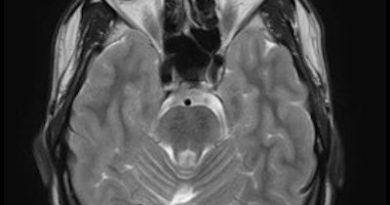

66 yaş, E

Kardiak arrest, 10 dk CPR öyküsü

24.03.2025 takip

Delayed posthypoxic leukoencephalopathy(DPHL)

Gecikmiş Post-hipoksik Lökoensefalopati (DPHL)

Gecikmiş posthipoksik lökoensefalopati (Delayed posthypoxic leukoencephalopathy)

Delayed posthipoksik lökoensefalopati.

Grinker myelinopati